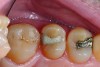

Fig 6. In Case 2, pretreatment view of multiple non-carious cervical lesions.

Fig 7. Cavities were cleaned with 20% polyacrylic acid solution.

Fig 8. Cavities were bulk-filled with high-viscosity auto-curing GIC.